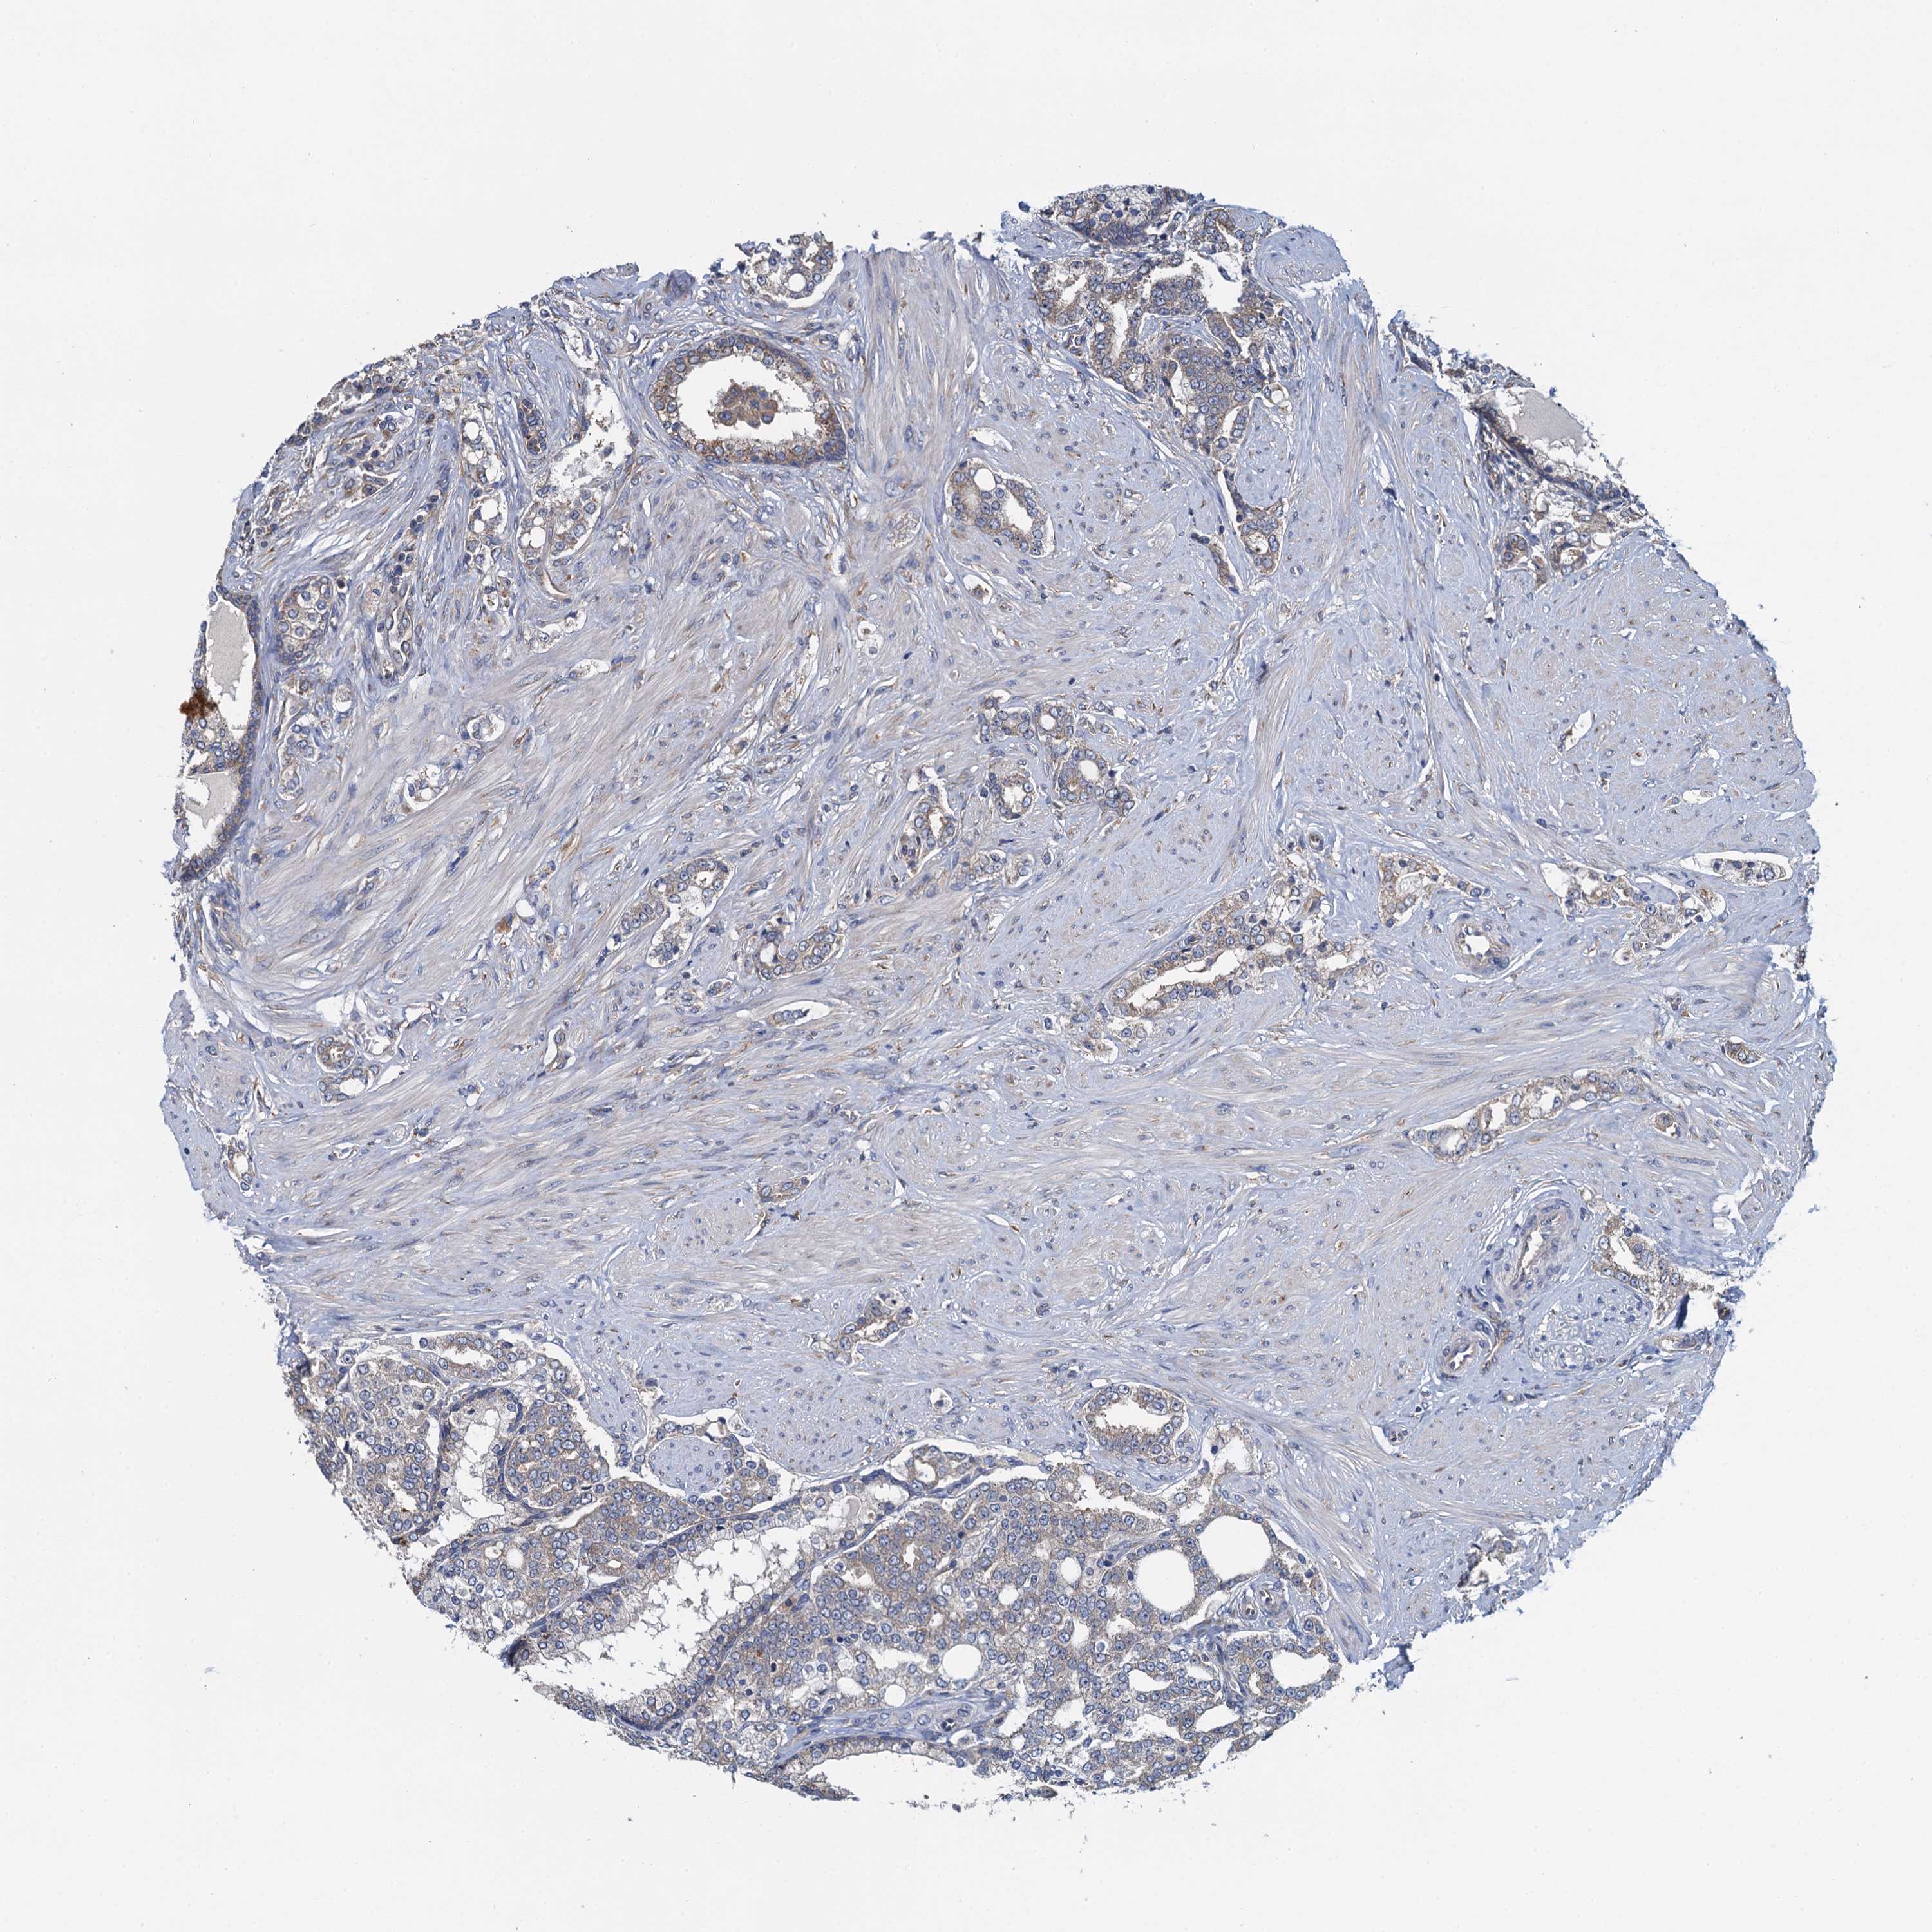

PROSTATE CANCER - Protein expressioni

A mouse-over function shows sample information and annotation data. Click on an image to view it in a full screen mode. Samples can be filtered based on level of antibody staining by selecting one or several of the following categories: high, medium, low and not detected. The assay and annotation is described here.

Note that samples used for immunohistochemistry by the Human Protein Atlas do not correspond to samples in the TCGA dataset.

Antibody stainingi

Antibody staining in the annotated cell types in the current human tissue is reported as not detected, low, medium, or high, based on conventional immunohistochemistry profiling in selected tissues. This score is based on the combination of the staining intensity and fraction of stained cells.

Each image is clickable and will lead to virtual microscopy that enables deeper exploration of all samples and also displays staining intensity scores, fraction scores and subcellular localization as well as patient and tissue information for each sample.

Antibody HPA041328

Antibody HPA044225

Staining

High

Medium

Low

Not detected

Intensity

Strong

Moderate

Weak

Negative

Quantity

>75%

75%-25%

<25%

None

Location

Nuclear

Cytoplasmic/membranous

Cytoplasmic/membranous,nuclear

Adenocarcinoma, NOS

Adenocarcinoma, High grade

Adenocarcinoma, Low grade